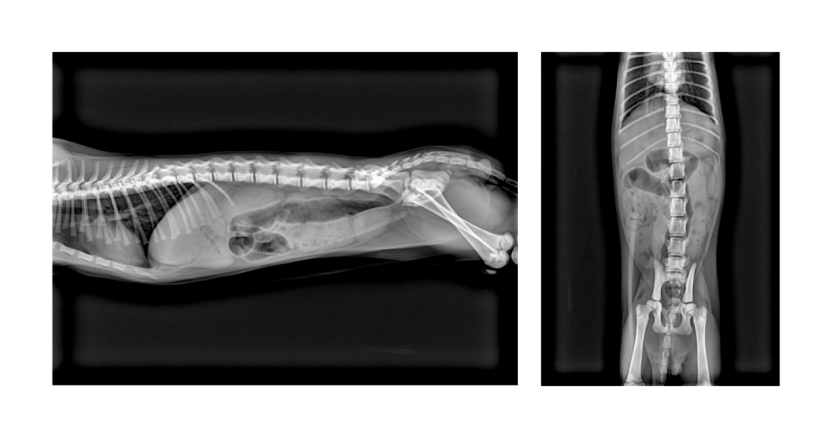

“我们接诊了一只 2 个月大的雄性阿比西尼亚猫‘Lucky’,主人主诉反复呕吐,初步人工阅片后并未发现明显异常,几乎要按普通病症处理。” 上海某宠物医院的医生在反馈中写道,“抱着试一试的心态调用了AI影像诊断,AI 诊断报告明确提示肠道内存在隐匿异物。我们立刻邀请专家再次复盘影像,最终确认异物存在,并紧急安排手术,成功为患宠取出了致命的异物。如果没有 AI 的精准提示,这例极易漏诊的病例很可能延误治疗,后果不堪设想。”

“上周接诊一只猫咪,我凭临床直觉怀疑存在异物与肠气,但反复人工阅片都没能找到明确证据。” 广州某宠物医院的医生分享道,“VetiDR 智能体判读结果却高度提示‘线状异物可能性大’,这让我们下定决心进行开腹探查。手术中果然发现有异物,及时为患宠解除了风险。AI 的敏锐度帮我们打破了人工阅片的经验盲区,也让诊疗决策更有底气。”